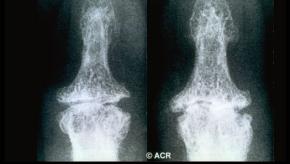

Read Article2023 EULAR classification criteria for hand osteoarthritis

A EULAR consensus group has established classification criteria for overall hand osteoarthritis (OA) and its subtypes (interphalangeal OA and thumb base OA).

The criteria require two mandatory criteria to be met: